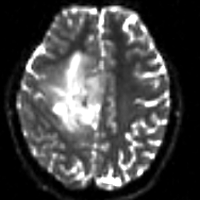

Registration Results

Registered DTI superimposed on SPGR and T2 original and registered pair of T1 and DTI (animated gif, may have to be opened to animate)